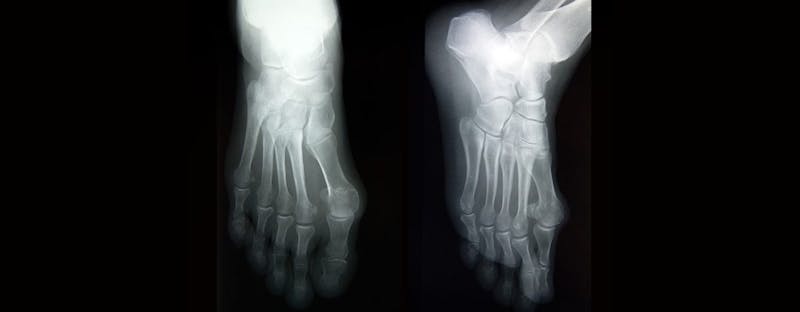

A Lisfranc injury is often misdiagnosed as a simple sprain. If the standard rest, ice, compression, and elevation therapy does not relieve your pain and swelling, you should see a foot doctor for further evaluation. During the physical exam, the doctor will perform several tests to determine if you have pain with certain movements that would indicate a Lisfranc injury. X-rays, MRIs, and CTs may also be used to determine the extent of your injury.